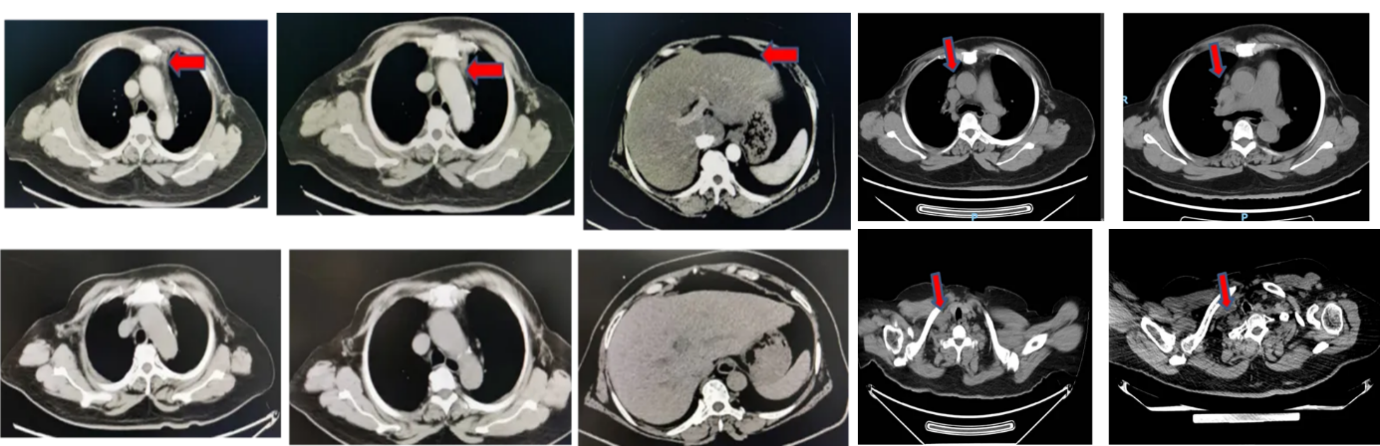

治疗方案:2018年1月至2020年1月,采用“长春瑞滨软胶囊(140mg d1、d8,Q3W)+卡铂(500mg d1,Q3W)”方案治疗。

疗效评价:治疗期间影像学评估达到部分缓解(PR)

PFS1:24个月

图片2.png

图2 2020年1月CT结果